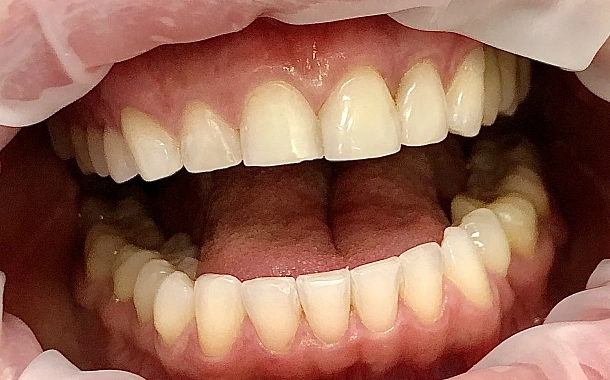

Для решения эстетических проблем передних зубов устанавливаются керамические накладки, или, по-другому, виниры. Они подбираются таким образом, чтобы придать зубам естественную белоснежность и красивую, ровную форму.

Установленные виниры совершенно не отличить от настоящих зубов, при этом они позволяют скрыть различного рода изъяны. Реставрацию зубов винирами используют, когда нужно скрыть или скорректировать:

сколы и трещины на зубах

неправильную форму зубов

увеличенные промежутки, щели между зубами, диастема

лёгкую скученность зубов

Изготовление винирова

Процесс изготовления керамических виниров состоит из нескольких этапов. Когда определены показания к восстановлению зубов винирами, снимается слепок зубов, отливаются лабораторные челюсти, моделируется макет будущих виниров. Затем с данных восковых реконструкций снимается дублирующий слепок, с помощью которого доктор изготавливает индивидуальный шаблон для препарирования зубов. Это позволяет препарировать зубы намного более щадящим и точным образом. После этого этапа зубной техник получает модель, на которой уже он готовит окончательные виниры. После этого доктору остается лишь зафиксировать готовые реставрации в полости рта пациента.Установка винира на зубы